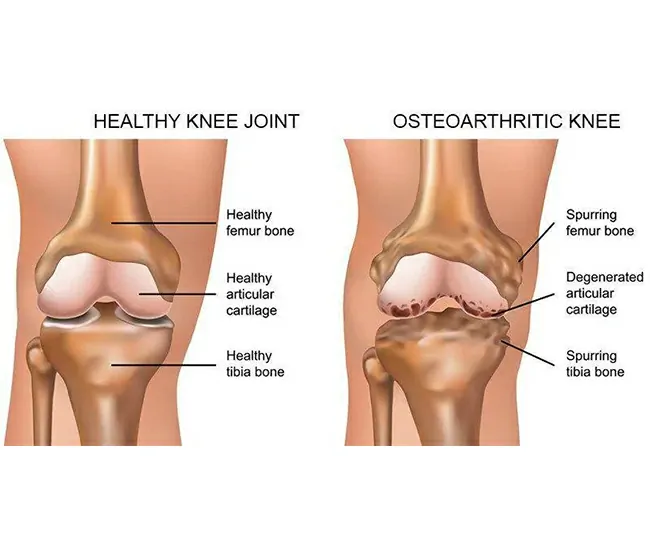

Knee osteoarthritis (OA) is a degenerative joint disease caused by the gradual breakdown of cartilage, ligaments, and bones in the knee joint. It leads to pain, stiffness, swelling, and reduced mobility.

1. Cartilage Degeneration – Loss of cushioning in the knee joint.

4. Osteophyte Formation (Bone Spurs) – Leads to stiffness & pain.